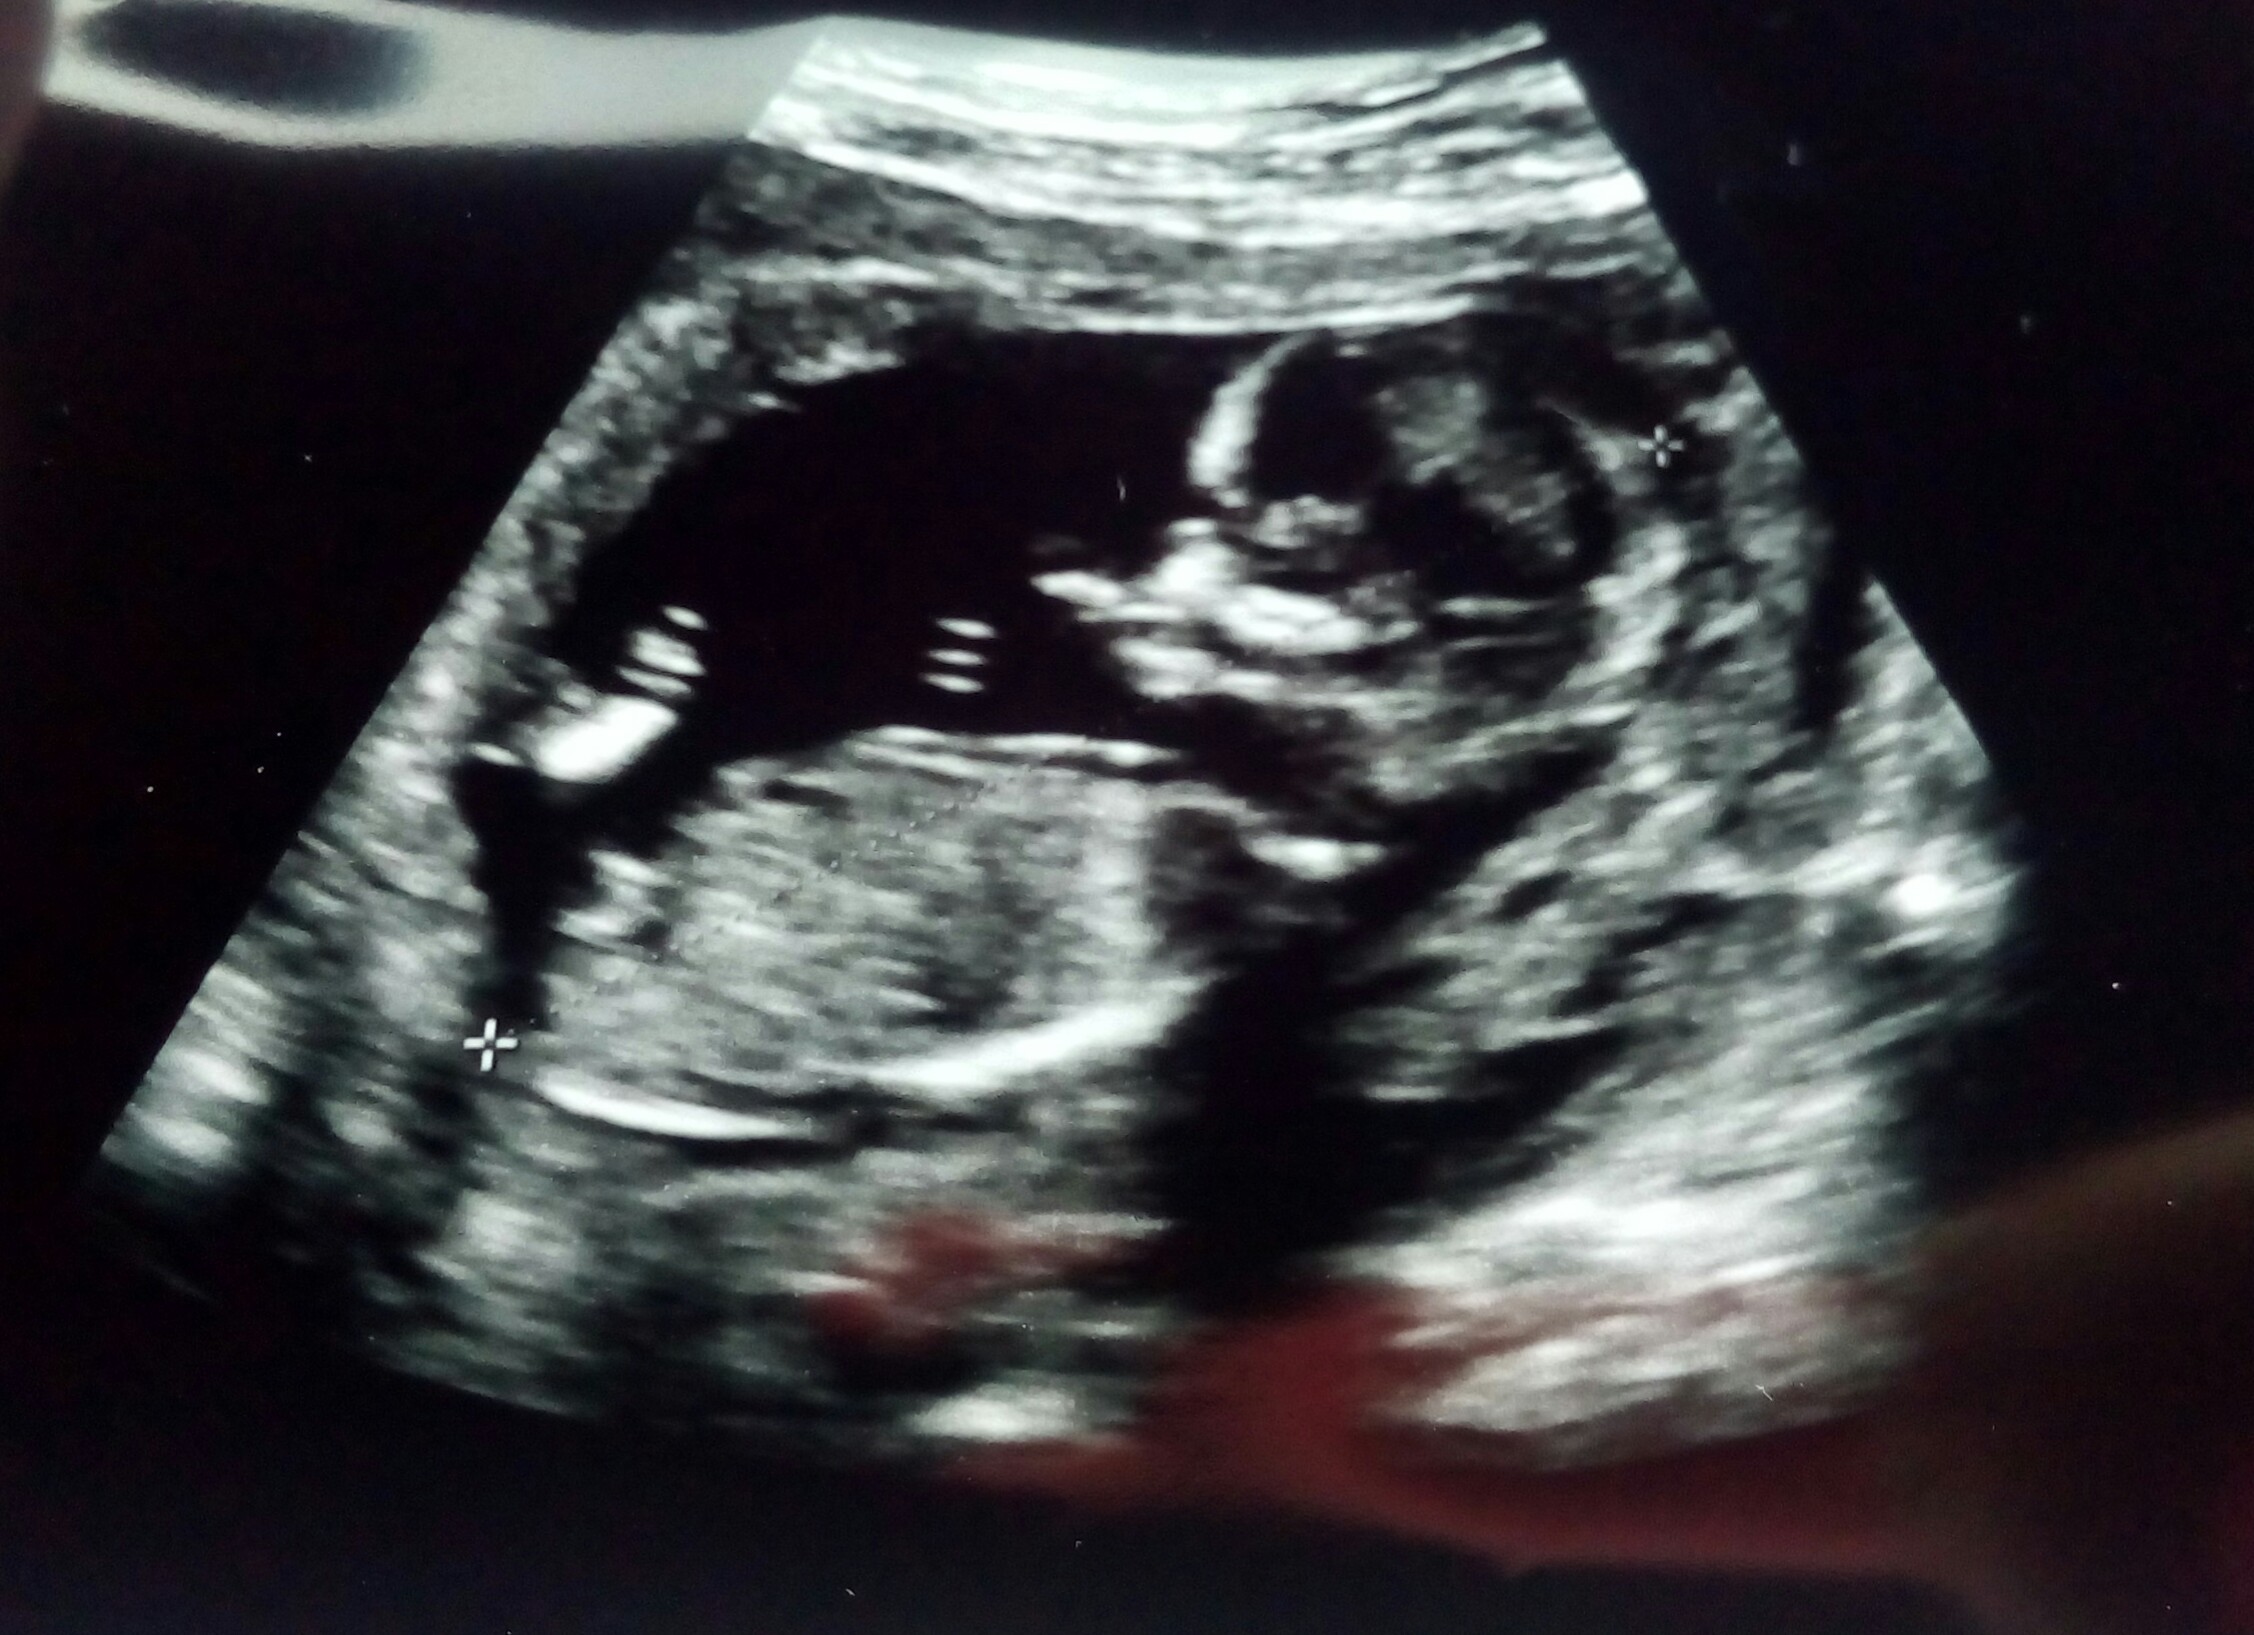

Zobacz załącznik 845840 Zobacz załącznik 845842

Maly ma 83mm

przeziernosc karkowa 1,2

Kosc nosowa widoczna

ogolnie wszystko w normie

Plci rowniez nie znamy